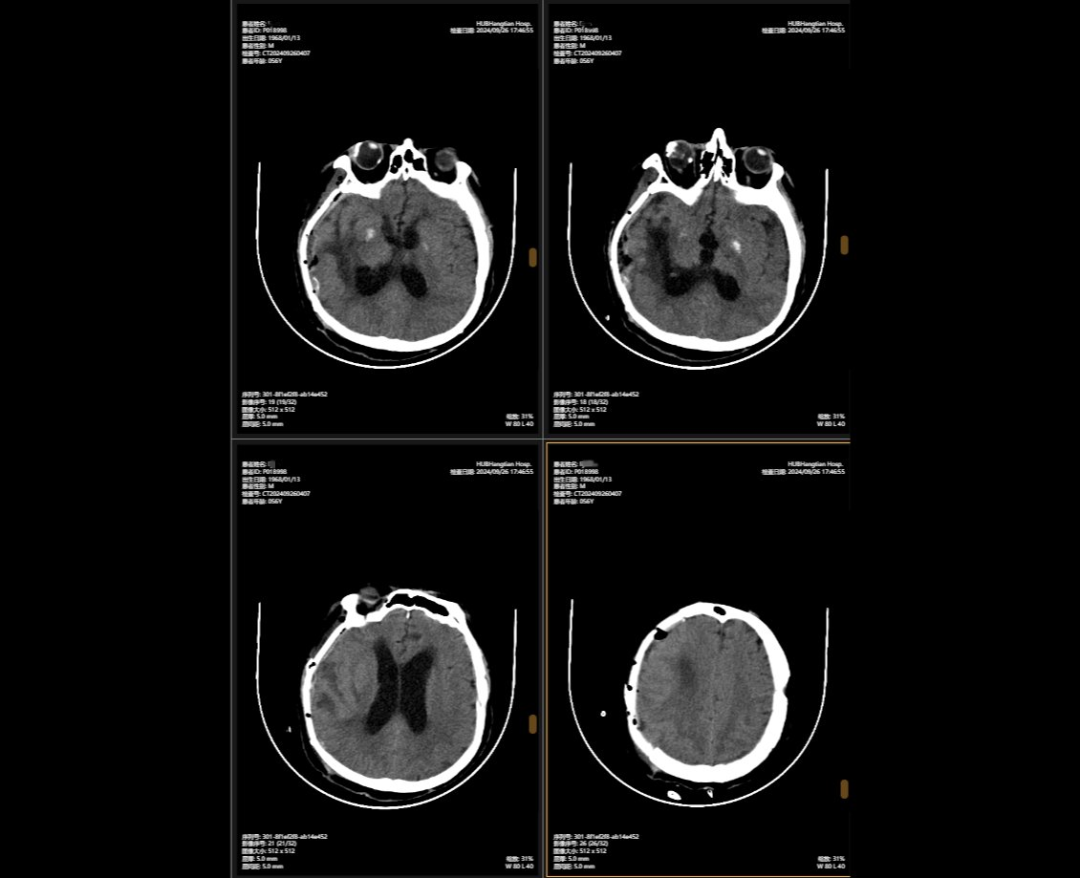

李先生的病情穩(wěn)定后,神外團(tuán)隊(duì)緊繃了數(shù)周的神經(jīng)終于得以松弛,他們隨即為他制定了顱骨缺損與腦積水治療方案,2024年9月,李先生接受了顱骨缺損修補(bǔ)術(shù),“修補(bǔ)”之前取下的頭骨,保護(hù)大腦,解決顱內(nèi)壓力不穩(wěn)問(wèn)題,術(shù)后他的神經(jīng)紊亂癥狀明顯改善;三個(gè)月后,神外團(tuán)隊(duì)繼續(xù)施行腦室-腹腔分流術(shù),通過(guò)植入的分流管,解決了腦積水問(wèn)題,讓腦壓恢復(fù)正常。

顱骨缺損修補(bǔ)術(shù)前術(shù)后對(duì)比